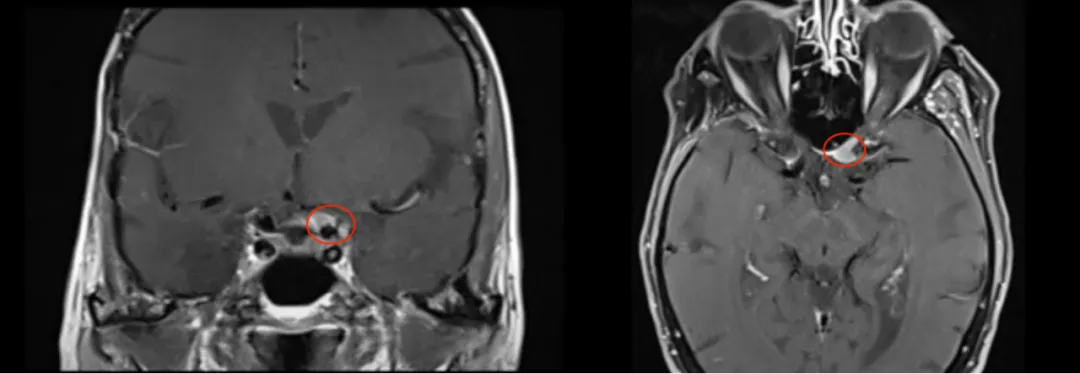

回顾过去,其实在2005年,Chloe就因右侧海绵窦区脑膜瘤做过一次开颅手术。这次就医检查发现左侧视力出现进行性下降,视力检查结果显示左侧视力为4.6(右侧5.0),左侧视神经管内侧病变呈现均匀增强。检查报告还显示翼点空化是由颞肌萎缩引起的,确诊脑膜瘤位于视神经管的中下侧,导致视力严重恶化。

Chloe术后核磁检查显示肿瘤完全切除,术中无功能神经损伤,无脑脊液渗漏等手术并发症,视神经保留完好,术后患侧视力也得到改善。